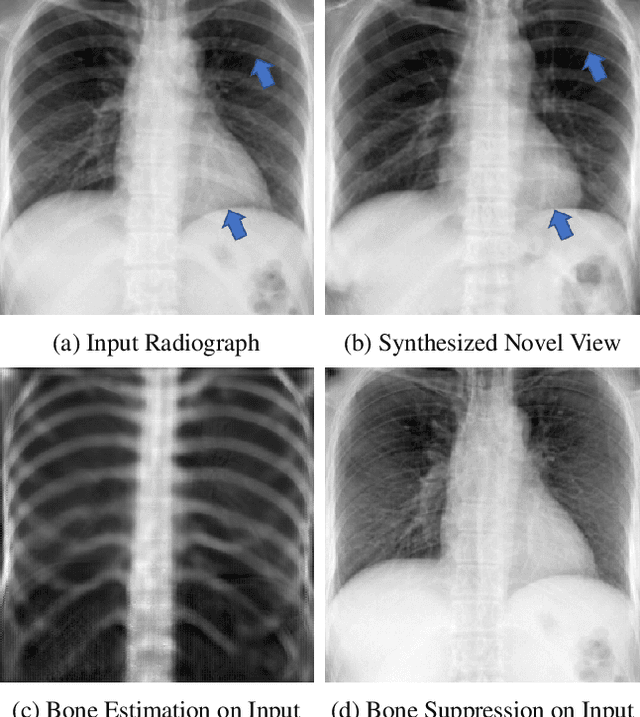

A radiograph visualizes the internal anatomy of a patient through the use of X-ray, which projects 3D information onto a 2D plane. Hence, radiograph analysis naturally requires physicians to relate the prior about 3D human anatomy to 2D radiographs. Synthesizing novel radiographic views in a small range can assist physicians in interpreting anatomy more reliably; however, radiograph view synthesis is heavily ill-posed, lacking in paired data, and lacking in differentiable operations to leverage learning-based approaches. To address these problems, we use Computed Tomography (CT) for radiograph simulation and design a differentiable projection algorithm, which enables us to achieve geometrically consistent transformations between the radiography and CT domains. Our method, XraySyn, can synthesize novel views on real radiographs through a combination of realistic simulation and finetuning on real radiographs. To the best of our knowledge, this is the first work on radiograph view synthesis. We show that by gaining an understanding of radiography in 3D space, our method can be applied to radiograph bone extraction and suppression without groundtruth bone labels.